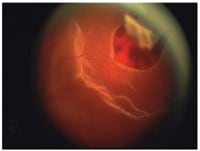

1. An image of a posterior retinal break where a primary vitrectomy is generally

utilized. IMAGES COURTESY OF KEVIN LANGTON, CRA, COLUMBIA OPHTHALMOLOGY PHOTOGRAPHY DEPARTMENT |

| Figure 2. An image of a giant retinal tear where a primary vitrectomy is generally utilized. |

Primary vitrectomy (with or without an encircling scleral buckle) is generally utilized in those eyes with vitreous hemorrhage, posterior retinal breaks (Figure 1), giant retinal tears (Figure 2), cataract or pseudophakic status, and established PVR. In eyes with diffuse pathology, often requiring extensive retinopexy in multiple quadrants, we feel vitrectomy may be a more ideal approach. By applying localized and focused retinopexy, and avoiding external drainage in the setting of a congested choroid, vitrectomy is extremely effective and safe. We often use a 3.5-mm solid, silicone-encircling element to support the posterior vitreous base in pseudophakic eyes, those with PVR, or those eyes with significant global peripheral pathology. However, if primary vitrectomy is being performed in a phakic eye with more limited pathology, such as a patient with a posterior retinal break, then scleral buckling is generally not required. In addition, we shave the vitreous base 360° under panoramic viewing in most patients. The retina is flattened internally utilizing perfluorocarbon liquids. Postoperative positioning is generally recommended for 1–2 weeks.